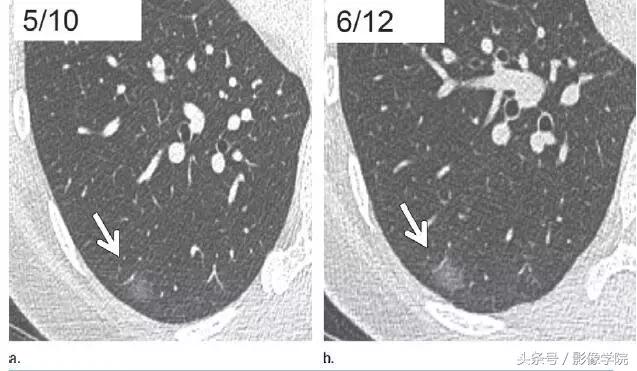

9、相隔 2 年的结节渐进表现

图 9 右肺下叶层厚 1 mm 的 CT 横断面图像,(a)显示边界清楚的 6 mm 大小毛玻璃样结节(箭头)。(b)2 年多后获得的图像,显示结节大小略有增加(箭头)。与相邻血管结构关系的轻微变化,证实了这一结果。这种微小进展只能通过层厚 1 mm 的连续扫描来发现。此类图像符合原位腺癌或微浸润腺癌表现,建议继续进行年度随访。